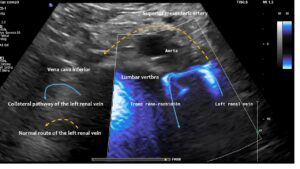

These images, taken from the front of the patient, show the tronc réno-rachidièn. This vessel runs in a U-turn along the left side of the lumbar spine towards the back, entering the intervertebral foramen and thus putting pressure on the spinal canal. They demonstrate that the preaortic portion of left renal vein (yellow dashed arrow) does not carry any blood, meaning that all of the left renal venous blood must be diverted via the tronc réno-rachidièn. The other natural collateral pathway, the left ovarian vein, is less significant here. In this patient ( as in many arteries with left renal vein compression) , the collateralisation via the left ovarian vein towards the pelvic venous circulation is obstructed by compression of the left common iliac vein. This combination is very common and requires simultaneous treatment of both the left renal vein and the left common iliac vein in one operation, by shielding both with a PTFE shield.

Blood within the tronc réno-rachidièn is modulated in a pulsatile manner, demonstrating rhythmic compression of the left renal vein between the aorta and superior mesenteric artery. This compression is so pronounced that no blood flow is visible ventral to the aorta only the pressure wave is transmitted towards the collateral vessel.

This image demonstrates the transfer of the pulsatile pressure of the aorta and the superior mesenteric artery towards the tronc réno-rachidièn (yellow arrows). Both arteries completely squeeze the final portion of the left renal vein obstructing the entire blood flow, but the pressure is rhythmically transferred towards the spinal canal and thus the spinal cord. Not rarely affected patients develop headaches and migraines which was not the case in this patient.